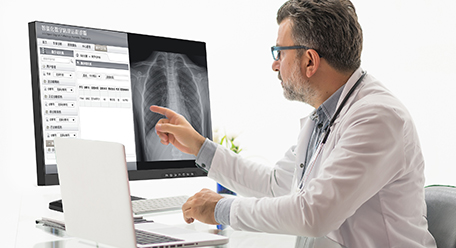

Monitor de radiodiagnóstico

Monitor de radiodiagnóstico

Áreas de aplicación: para sala de hacer la foto de radiología / sala de lectura / estación de imagen radiológica